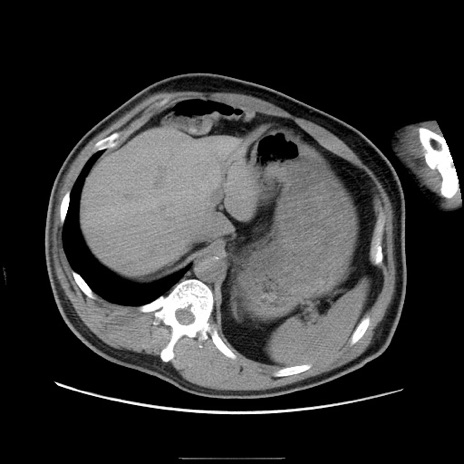

症例22(横断像)

【症例】50歳代男性

【主訴】腹痛

【現病歴】AVMからの被殻出血のため回復期リハ病棟入院中。 本日午後3時頃急に下腹部痛が出現した。

【既往歴】AVM、被殻出血、虫垂炎、高血圧

【身体所見】意識晴明、左半身不全麻痺、会話の理解は良好、36.5°C、腹部:膨隆、全体に板状硬、下腹部正中に圧痛点あり、反跳痛-、筋性防御不明、右下腹部にope scar

【データ】WBC 9400、CRP 0.06